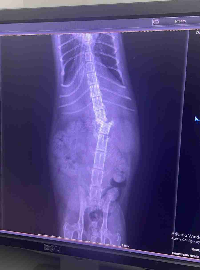

Olá,eu sou o gigio,e fui atacado por 5 cães,no condomínio onde fui abandonado,por conta disso perdi os movimentos das minhas perninhas, estou em um lar temporário pago com ajuda de doações,pois corria o risco de ser sacrificado a pauladas,agora preciso da sua ajuda para realizar a cirurgia da minha coluna, pois sinto muitas dores,e tenho muita chance de voltar a andar,o valor inclui, exames, cirurgia e fisioterapias,sou um gatinho cheio de gratidão ,

e vontade de viver,por favor me ajudem a voltar a correr e brincar novamente 🙌🏻🙌🏻